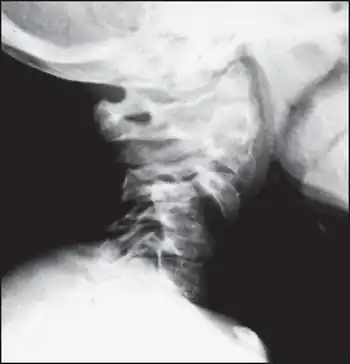

| Hypoplasia of C5 vertebral body and anterior luxation of C4 | |